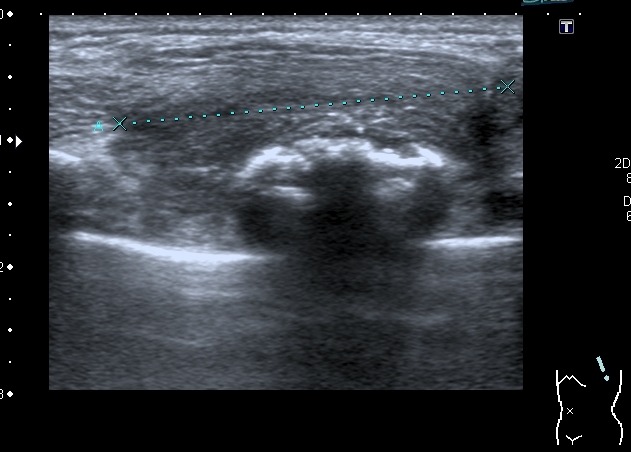

На УЗИ - такая картинка:

Деструкция корткального слоя 7-го ребра с ткаенвым компонетом, исходящим из кости. 7th rib destruction with solid mass

Поперечный скан. Transverse scan

образование оттесняет сосуд,  в самом кровоток достоверно не определяется. No bloodflow in mass is detected.